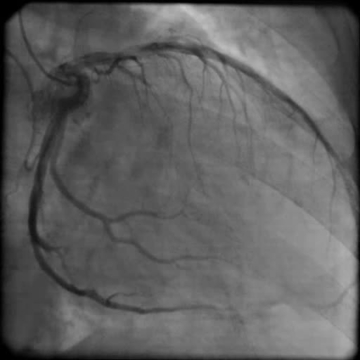

Při fyzikálním vyšetření měla nemocná TK 115/70 mm Hg, pravidelný puls 100/min, poslechově na plicích inspirační chrůpky při bázích a systolický šelest v prekordiu s maximem na hrotu, bez jasné propagace, intenzity 3/6. Dolní končetiny jsou se symetrickými perimaleolárními otoky, klidné varixy. Na EKG byla přítomna sinusová tachykardie 105/min, EKG kritéria hypertrofie levé komory s mírnými repolarizačními změnami, bez signifikantní ST denivelizace a abnormalita levé síně (obrázek 1). Echokardiografie prokázala dilataci a excentrickou hypertrofii levé komory (LVEDD 63 mm, LVMI 102 g/ m2, relativní tloušťka stěn 0,35), difúzní hypokinezi stěn výraznější v oblasti septa a těžkou systolickou dysfunkci levé komory s EF 24 %. Diastolická funkce měla charakter pseudonormalizace se zvýšenými plnicími tlaky levé komory (E/e'průměr 13). Dále byla zjištěna středně významná sekundární mitrální regurgitace 2–3+ při dilataci anulu a restrikci cípů v důsledku remodelace levé komory a sekundární trikuspidální regurgitace 2–3+ při dilataci anulu (video 1 a 2). Levá síň byla dilatována s indexovaným objemem 48 ml/m2 a zvýšena byla tenze v plicnici s odhadem PASP 49 mm Hg. Laboratorně prokázána elevace NT-proBNP 4 170 ng/l, mírná hypokalémie 3,6 mmol/l, kreatinin 112 μmol/l s mírně sníženou glomerulární filtrací 70 ml/min/1,73 m2 dle MDRD.

Video 1. Echokardiografické vyšetření, apikální čtyřdutinová projekce (1A) a dvoudutinová projekce (1B) – dilatace a významná systolická dysfunkce levé komory s EF 24 %